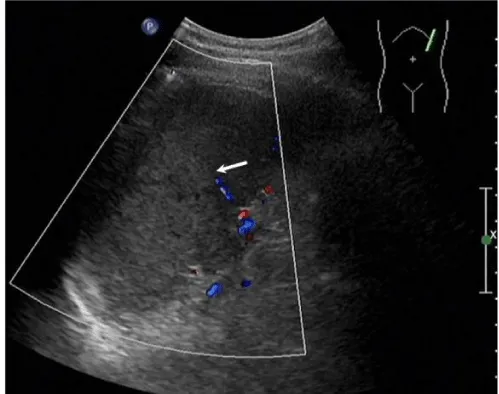

Solitary well-circumscribed masses were detected in all the five patients by ultrasound. One mass was of hypoecho, while the remaining masses were of hyperecho with posterior enhancement (Figure 1A). The maximum diameter ranged from 3.0 cm to 9.0 cm. At CT scanning, two masses appeared as hypodense (Figure 1B) and one was isodense (Figure 2A) to the normal spleenic parenchyma. In the two patients who received MR imaging, masses were isointensity at T1 weighted images (Figure 3A) and hypointensity with scattered sign void spots at T2 weighted images (Figure 3B). After intravenous injection of the contrast materials, all the five masses presented circle enhancement at arterial phase (Figure 3C and Figure 4A), while peripheral enhanced node was noted in one mass (Figure 2B). The circle enhancement persisted and radical line enhancement were observed at portal vein phase in 3 cases (Figure 1C) and progressive filling in was seen in two cases (Figure 2C). At delay phase of MR imaging, one lesion showed obvious enhancement with stellate low signal scar in the center comparing with surrounding splenic parenchyma (Figure 3D), while the other demonstrated central and circle enhancement to form a spoke-like appearance (Figure 4B). At delay enhanced CT scanning, two masses were isoattenuation to the surrounding splenic parenchyma (Figure 2D) and one lesion kept as hypoattenuation but with radial enhanced lines and enhanced circle to form a spoke-like appearance.